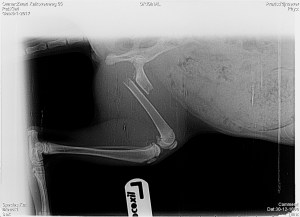

rontgen-kiwi-1‘Een gezond katje, zo jong, met een botbreuk die goed te opereren is? Ik denk er niet aan om haar te laten inslapen,’ reageerde de jonge dierenarts verontwaardigd. Op mijn onnozele vraag of we ook niets zouden kunnen doen, werd zij ronduit boos. Toen ik later de foto’s zag, begreep ik waarom. Voorzichtig legde ik uit dat in mijn veronderstelling inslapen vroeger een stuk normaler was. Dat beaamde de dierenarts, maar zij had een eed afgelegd en daar zou zij naar eer en geweten naar handelen. rontgen-kiwi-2Er waren vast dierenartsen die het wel zouden doen, maar ik zou moeite moeten doen om er één te vinden.

We mochten bij Kiwi kijken. Ze was nog wat suf van de narcose, maar verder ging alles goed met haar. Op de röntgenfoto zagen wij hoe een stalen pin haar dijbeen weer bij elkaar hield. We bedankten de dokter en rekenden af met pijn in ons hart. We hadden geen andere keuze gehad dan deze en het was de juiste keuze. Op weg naar huis vroeg ik me wel af of wij voor hetzelfde geld niet een mensenleven in het land van de kikkers voorgoed hadden kunnen veranderen.